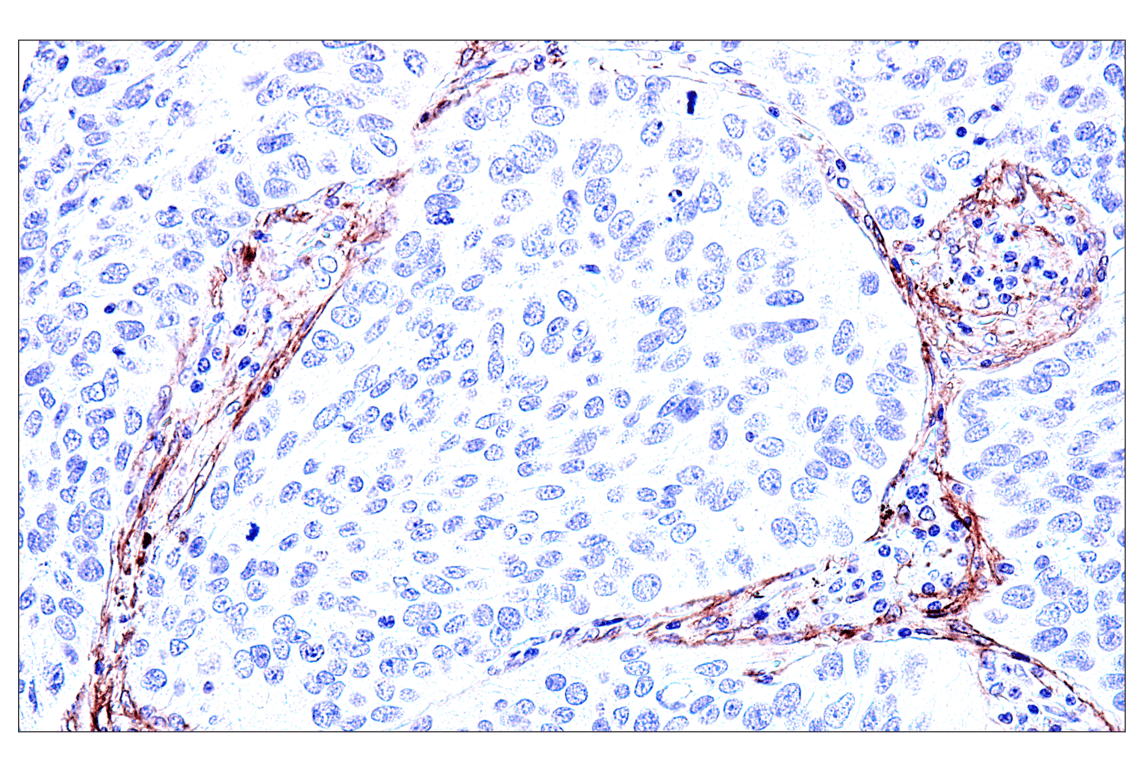

Immunohistochemical analysis of paraffin-embedded human Ewing sarcoma using FAP (F1A4G) Rabbit mAb. Data were generated using the standard formulation of this product.

Immunohistochemistry Image 3: FAP (F1A4G) Rabbit Monoclonal Antibody (BSA and Azide Free)